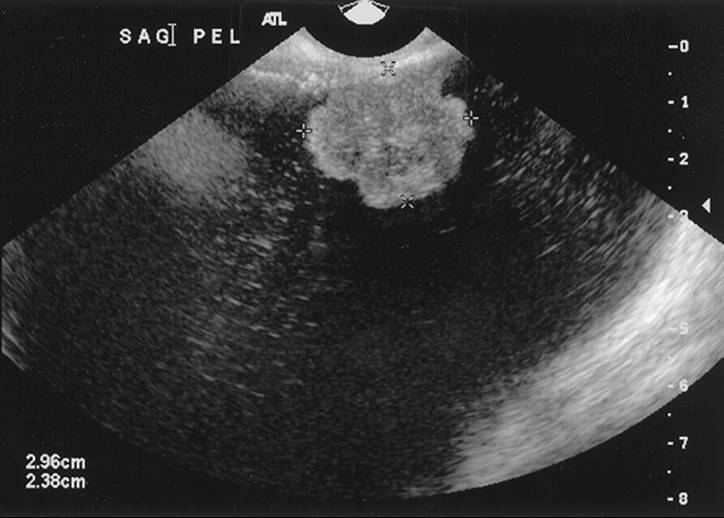

An ultrasonographic evaluation can clarify the etiology of the mass. Although not definitive, suggestions that the masses may arise from the tube, such as the form of hydrosalpinges or tuboovarian abscesses, can be helpful. This is operator dependent and, as such, obtaining an ultrasonographic examination from a quality center would be of utmost importance in managing patients with adnexal masses (Fig. 56.3 and Fig. 56.4).

FIG. 56.3. Ultrasonographic image of a tuboovarian abscess.

FIG. 56.4. Ultrasonographic image of a cystadenofibroma.